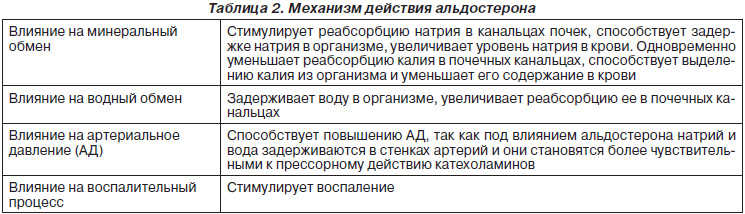

Альдостерон — основной минералокортикоид человека, регулирующий водно-солевой обмен, в первую очередь обмен ионов натрия, калия, водорода. Секрецию альдостерона регулирует главным образом концентрация калия в сыворотке крови и активность ренин-ангиотензиновой системы. Адренокортикотропный гормон (АКТГ) имеет незначительное влияние на секрецию альдостерона. Избыток минералокортикоидов обусловливает артериальную гипертензию, а недостаток — гиперкалиемию, которые могут оказаться несовместимыми с жизнью (табл. 2).